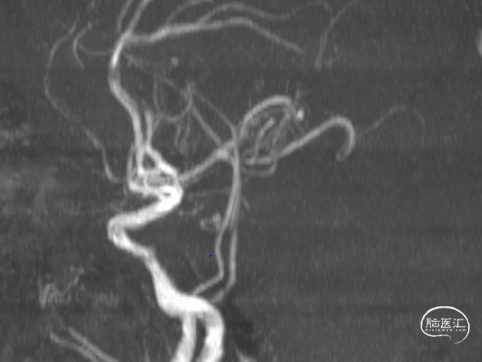

1.急查头颅MRI+RMA示:

2.右侧小脑半球、双侧枕叶、左侧颞叶脑梗塞;

3.桥脑区、双侧基底节区陈旧性脑梗塞;

4.脑白质脱髓鞘;

5.双侧椎-基底动脉、双侧大脑后动脉、右侧大脑前动脉闭塞;

6.右侧颈内动脉狭窄;

7.脑动脉硬化。

MRI

MRA